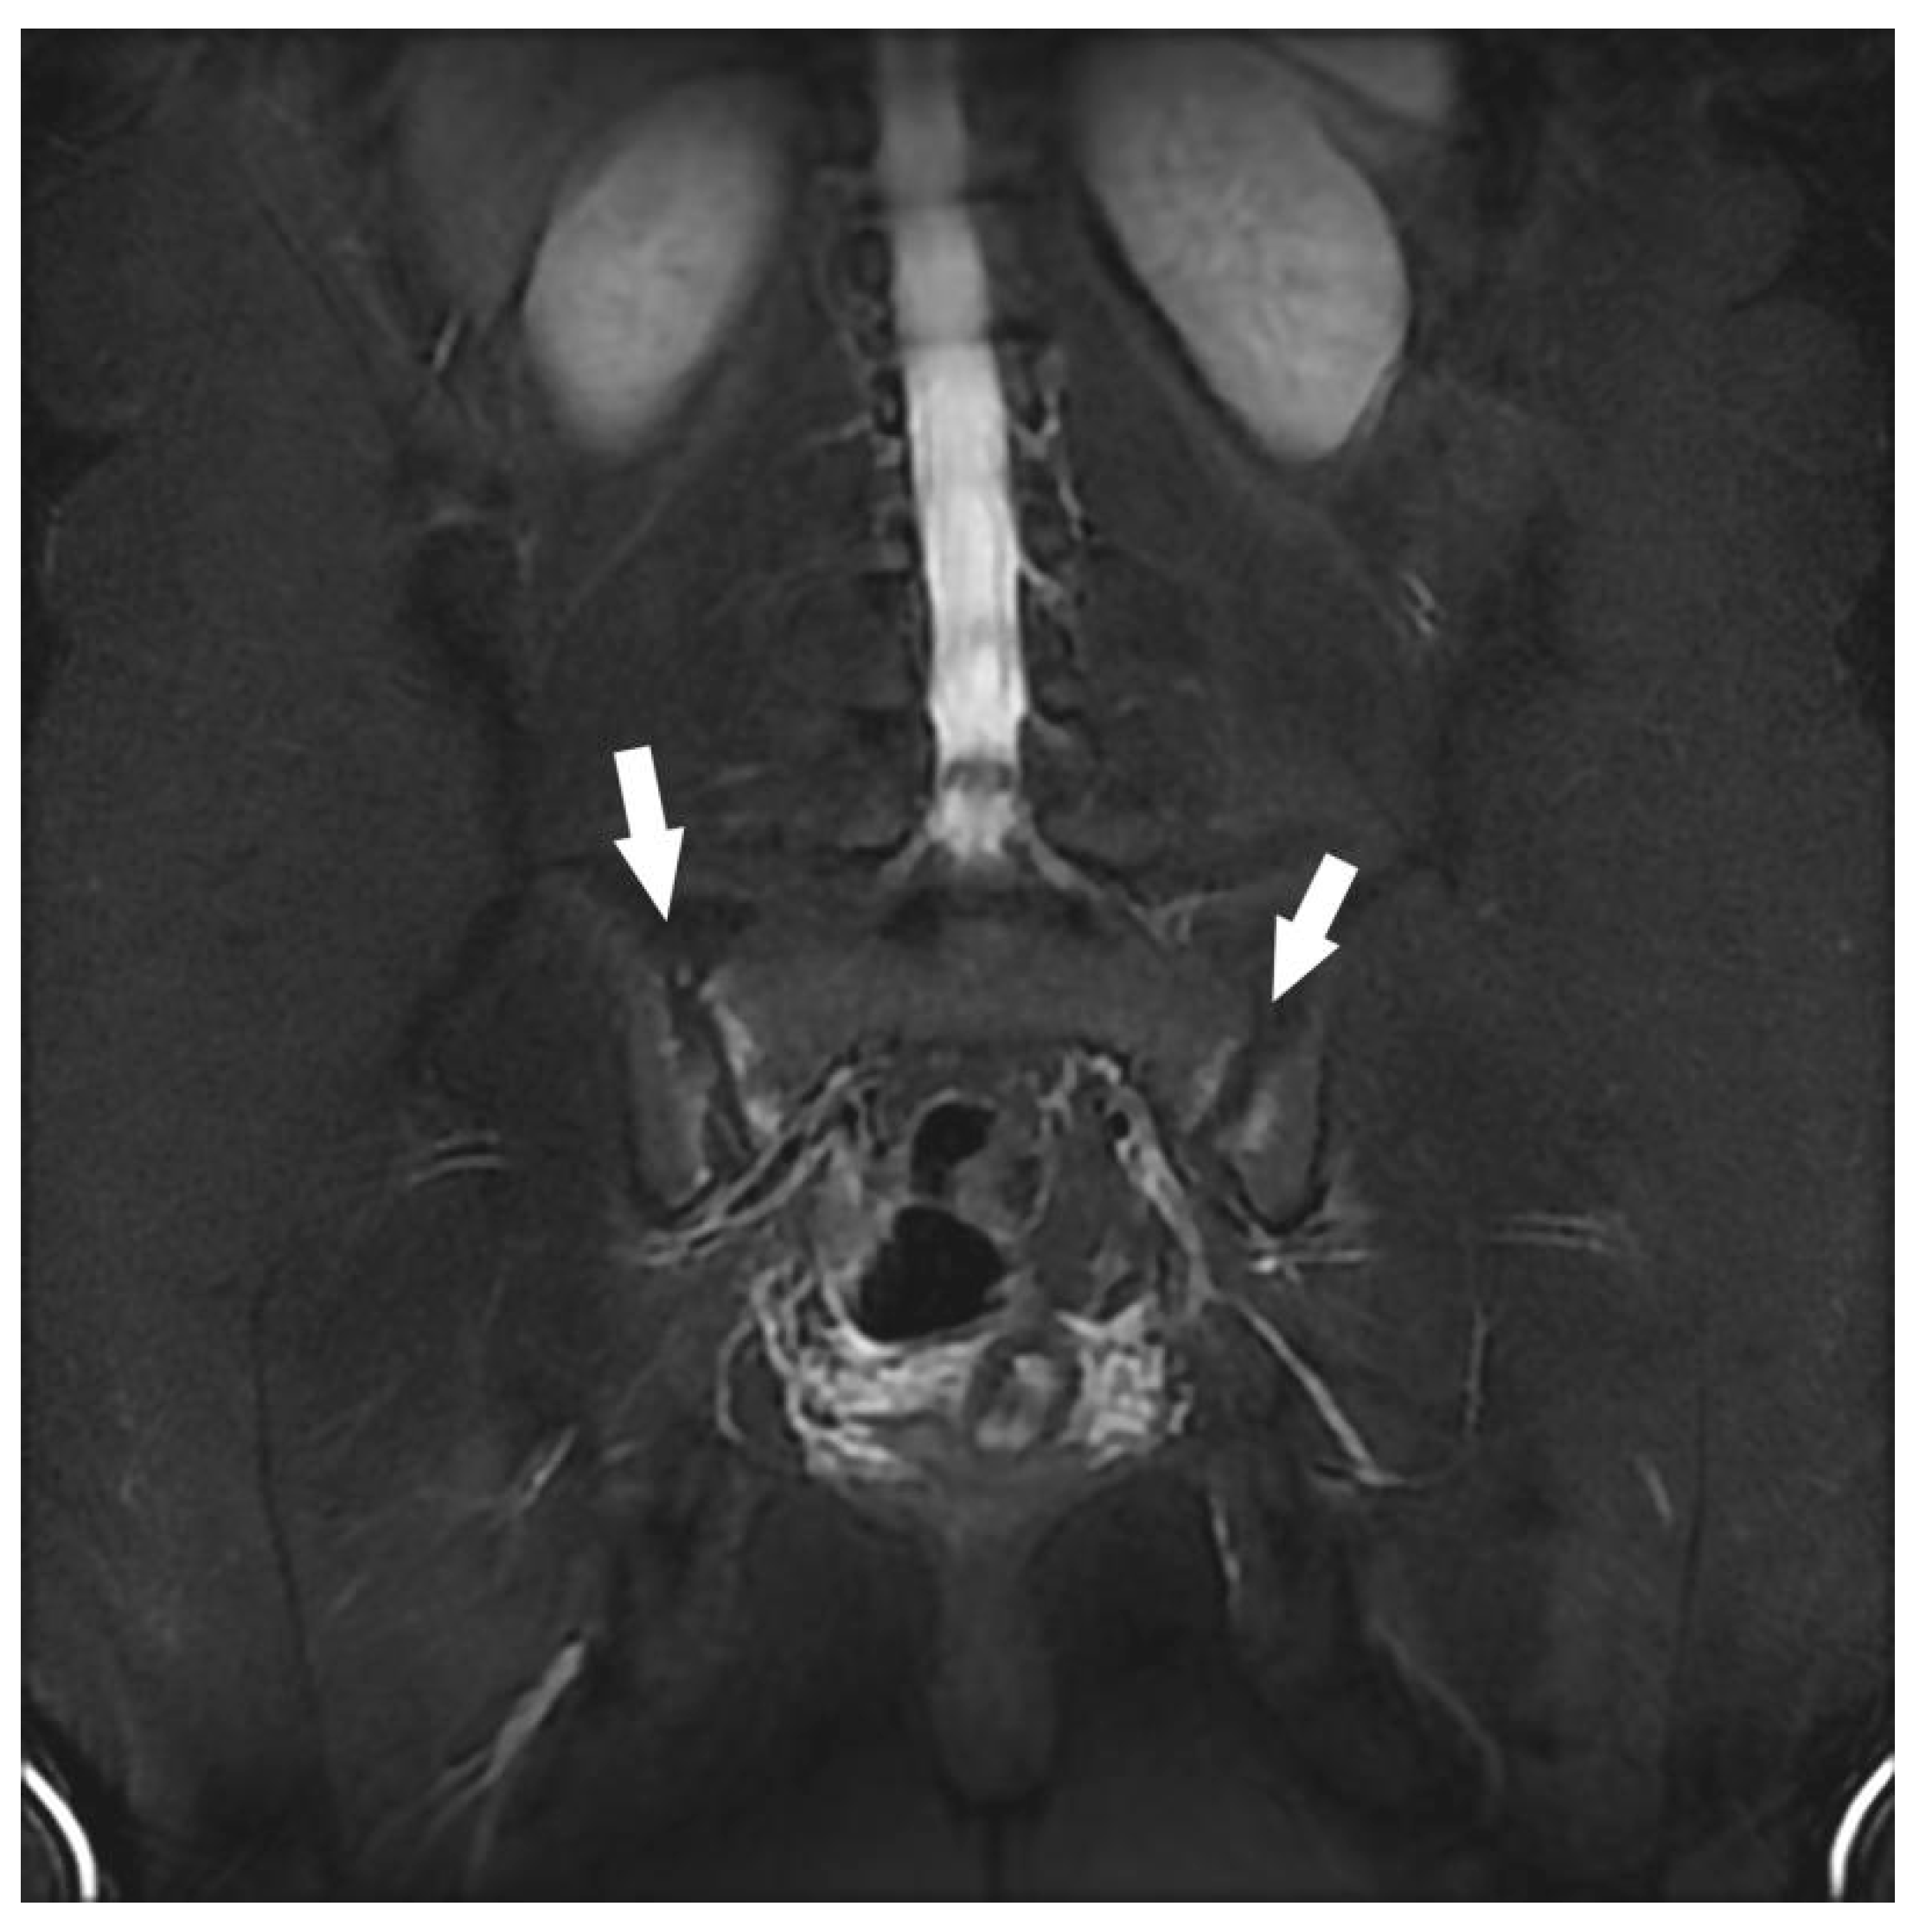

| Sacroiliac Joint | Congestive degenerative arthropathy | 10 |

| Inflammatory sacroiliitis | 4 | |

| Sacral fracture | 1 | |

| Congestive degenerative sacroiliac arthropathy 2 | 8 | |

| Atypical bone lesion (iliac wing, femoral neck, sacrum) 1 | 3 | |